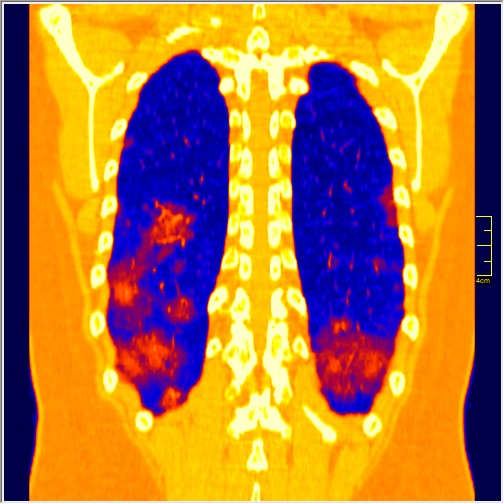

Kako sam radiolog moja nauka se izražava kroz slike. Ovo su pacijenti pregledani samo u jednom danu, godišta od 1991. do 1999.

Kao što sam rekao, slike govore sve. Ono što se razlikuje od ranijih pacijenata je obavezna hilarna limfadenopatija i gustina ground glass promena već u prvoj fazi. Ono što mi kliničari kažu je da ide sa visokom temperaturom, čak i preko 40 i da su svi simptomi izraženiji, sem gubitka čula mirisa i ukusa, koje je retko.